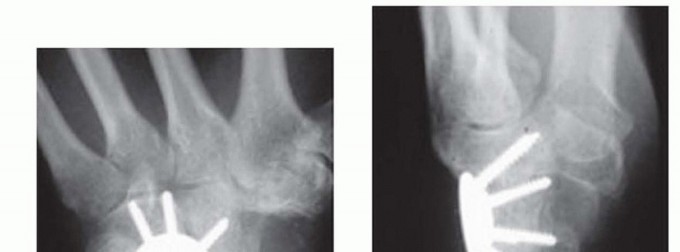

TECH FIG 5 • Scaphocapitate fusion construct using two headless, cannulated compression screws. Note the addition of a radial styloidectomy. (Fingers are at top.)